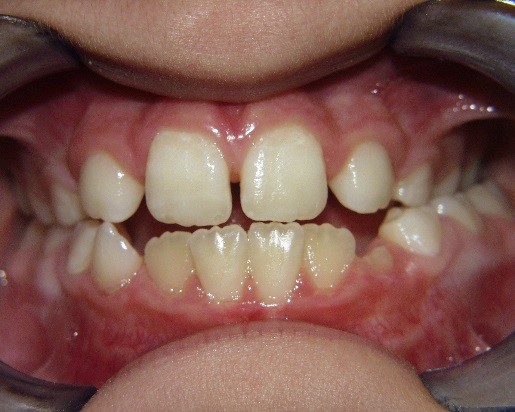

Key #2: An expander during the early mixed dentition allows the primary teeth to anchor the expansion appliance. This has significant benefits for permanent dentition that eliminate potential adverse effects, including dehiscence of the buccal bone, gingival recession, and root resorption. Expansion appliances use the strength of the roots and surrounding bone of the teeth to which they are attached. Consequently, those teeth and supporting bone carry the lateral pressure of the expansion as the suture opens. When primary teeth support the expander, the succedaneous bicuspids and canines do not bear any expansion pressure. The newly erupting teeth only benefit from the additional space development the expander has created. The acrylic bonded expander is easily constructed to adapt exclusively to the primary dentition, and has the added benefit of spreading the attachment over several teeth on each side. A banded hyrax appliance can be attached to the second primary molars and canines, or the permanent first and primary first molar. Studies have reported that using a Haas expansion appliance attached to the second primary molars and primary canines is successful and stable.